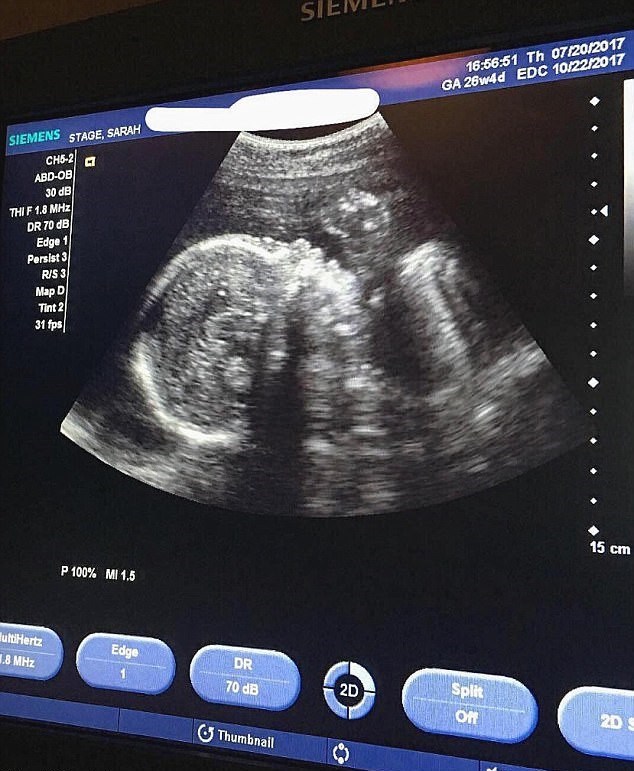

Восьмой месяц, это время третьего, последнего скринингового обследования. Предстоит УЗИ, которое даст детальную информацию врачам, но не будет особо интересен будущей маме, ведь малыш большой настолько, что не помещается на мониторе специального аппарата. Вы не видите ребенка полностью.

УЗИ на этом сроке назначается для проверки развития плода, состояния околоплодных вод и плаценты. Исследование может назначить врач при подозрениях на неблагополучное течение беременности, можно прийти УЗИ по собственной инициативе. Ребёнку хуже не будет, а вы немного успокоитесь.

Третье УЗИ при беременности проводят в 8 месяцев. Собственно, восьмой месяц достаточно часто становится временем проведения последнего планового УЗИ. Задачи УЗИ при беременности накануне родов заключаются в следующем:

Начало 8 месяца беременности это время последнего, третьего скринингового обследования. Вам предстоит третье УЗИ, которое даст очень много информации врачам, но на котором будущей маме будет почти не интересно, малыш уже такой большой, что не помещается на мониторе аппарата, и вы не сможете его увидеть полностью, как на предыдущих УЗИ.